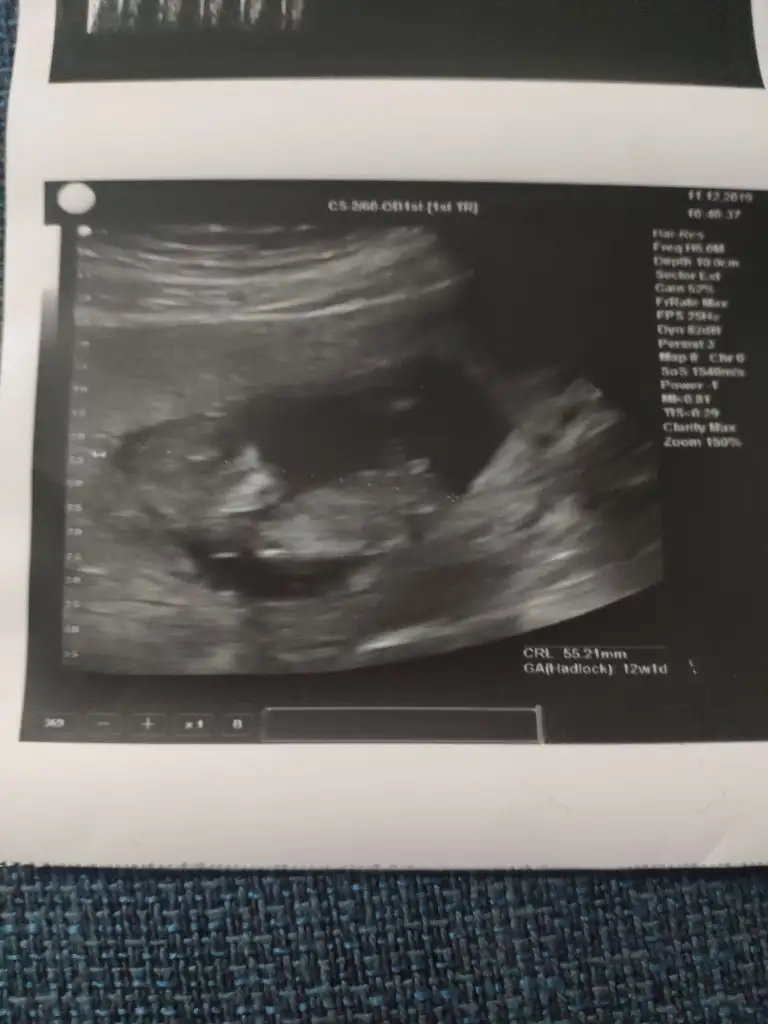

Buda bizim Nub umuz bı tahminde bulunur musunuz ☺️ bıraz karanlık cıktık ama olabıldiği kadar. Dr erkek dedı ilerleyen zamanda netlestırrız dedı. Sızcede oylemı tesekkürler .